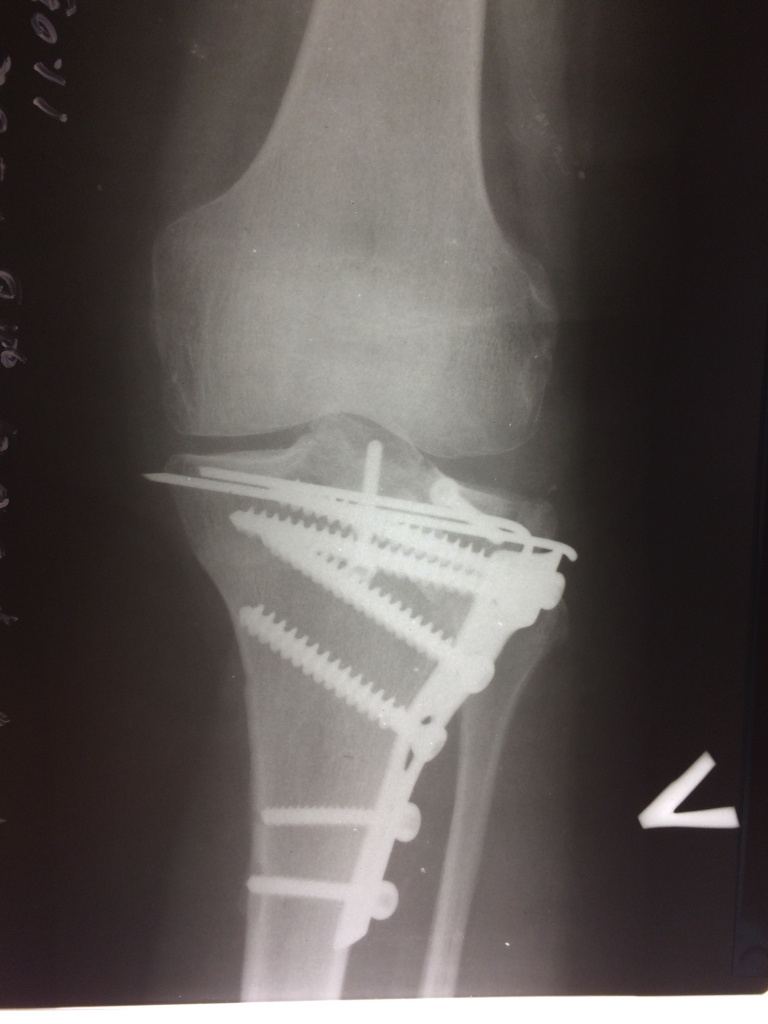

Использование материала Остеоматрикс при импрессионном оскольчатом переломе наружного мыщелка большеберцовой кости по типу Schatzker II

Использование материала Остеоматрикс при импрессионном оскольчатом переломе наружного мыщелка большеберцовой кости по типу Schatzker II.

Операция - открытая репозиция, остеосинтез большеберцовой кости опорной пластиной с костной ксенопластикой маетриалом "Остеоматрикс". На контрольных снимках в три и шесть месяцев имеется консолидация перелома, миграции фиксатора нет, имеется остеоинтеграция ксенопластического материала. Функция коленного сустава полная.